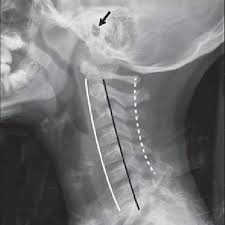

This procedure may be used to diagnose back or neck pain, fractures or broken bones, arthritis, degeneration of the disks, tumors, or other problems. Enter search terms and tap the search button. They show pictures of your internal tissues, bones, and organs. Please understand that our phone lines must be clear for urg. Here's what to expect with this painless procedure and why your dentist may recommend it.

This procedure may be used to diagnose back or neck pain, fractures or broken bones, arthritis, degeneration of the disks, tumors, or other problems. It's commonly done after someone has been in an automobile or other accident. They show pictures of your internal tissues, bones, and organs. Here's what to expect with this painless procedure and why your dentist may recommend it. Please understand that our phone lines must be clear for urg. Enter search terms and tap the search button.